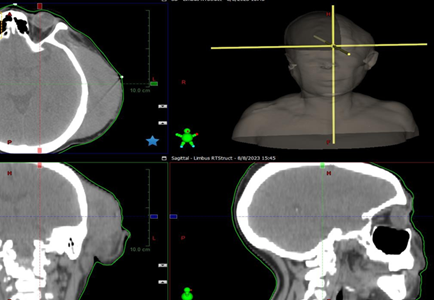

fissure effacement and mild subfalcine midline shift. (Figure 1) shows a cross-sectional cut of the brain through the

mass and a 3D rendering of the CT scan showing left sided mass.

Figure 1.

Cross-sectional cut the head

showing the tumor and 3D reconstruction.